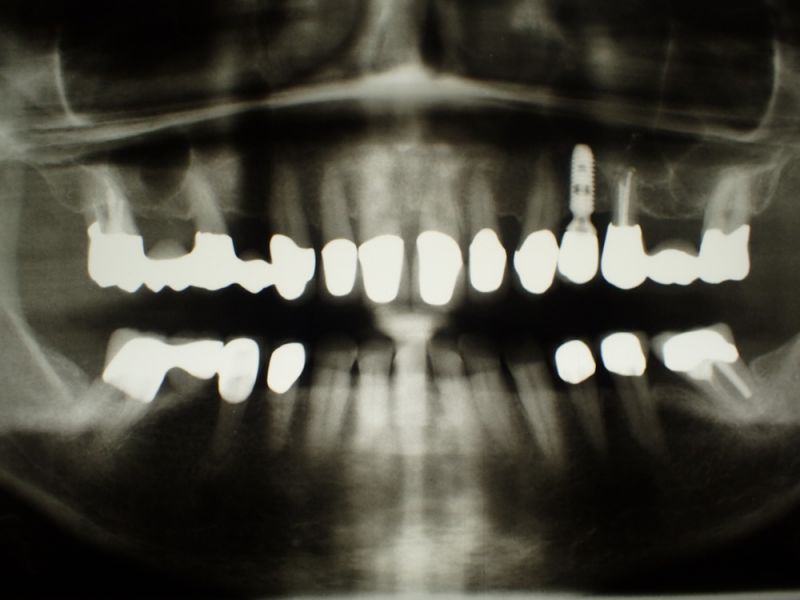

Erste Planungen für eine CMD Patientin mit 25 Jahre inkorporierter Restauration (Podcast)

Die bestehende funktionstherapeutische Versorgung befindet sich nunmehr seit 25 Jahren im Munde der Patientin und der ist bewusst, dass das zwar ganz toll ist, aber aus verschiedenen Gründen nicht davon auszugehen ist, dass die Versorgung in ihrer ganzen Komplexität nochmal 25 Jahren funktionieren dürfte.

Dabei ist das Problem nicht primär die zahntechnische Rekonstruktion, sondern die Fundamente, die schon vor 25 Jahren nicht mehr taufrisch waren und nun zwar durch guten und regelmäßigen, vierteljährlichen Recall, 25 Jahre lang ununterbrochen in Schuss gehalten werden konnte, aber eben auch eine begrenzte Lebensdauer besitzen.

Ab der zweiten Jahreshälfte, wenn die Patientin dann in einen neuen Lebensabschnitt eintritt, werden nun erste konkrete Planungen beginnen, mit dem Ziel, über die kommenden Jahre hinweg bestehende, aber ebenlangfristig nicht zu erhaltbare Fundamente, sprich Zähne, gegen belastbare Implantate auszutauschen, um dann, wenn genügend belastbare Fundamente vorhanden sind, darauf dann einen neuen funktionstherapeutischen Zahnersatz zu installieren, der dann weitgehend bis ans Lebensende der Patientin halten möge.